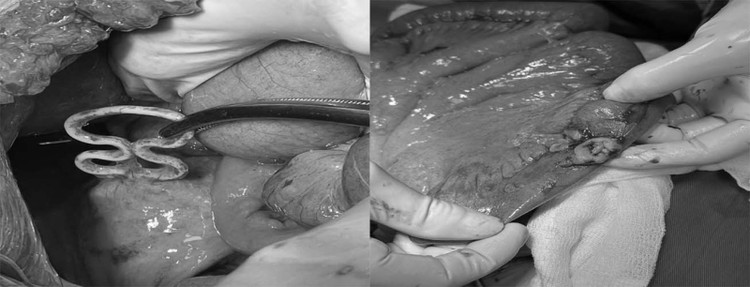

| Dụng cụ tử cung lạc chỗ đâm xuyên tử cung, thủng ruột non - Ảnh BVCC |

BSCKII Dương Xuân Hiệp – Trưởng Khoa Ngoại Tổng hợp, BSCKI Tô Thị Kim Quy – Trưởng Khoa Phụ Sản, Bệnh viện Bãi Cháy đã tiến hành phẫu thuật cấp cứu xử trí tổn thương cho người bệnh. Quá trình phẫu thuật quan sát thấy ổ bụng bẩn có dịch đục, thức ăn, thân tử cung mặt trước có dụng cụ tử cung dạng vòng số 8 (1/3 vòng cắm trong cơ tử cung 2/3 vòng nằm ngoài tử cung), quai ruột non vị trí sát thân tử cung rách ngang kích thước khoảng 2cm, đang thoát dịch tiêu hóa.

Các bác sĩ đã tiến hành lấy dụng cụ tử cung trên cơ tử cung, khâu phục hồi cơ tử cung, lỗ thủng ruột non, cầm máu, lau rửa và đặt dẫn lưu ổ bụng. Sau phẫu thuật 24h, sức khỏe bệnh nhân ổn định và được theo dõi sát quá trình hồi phục.